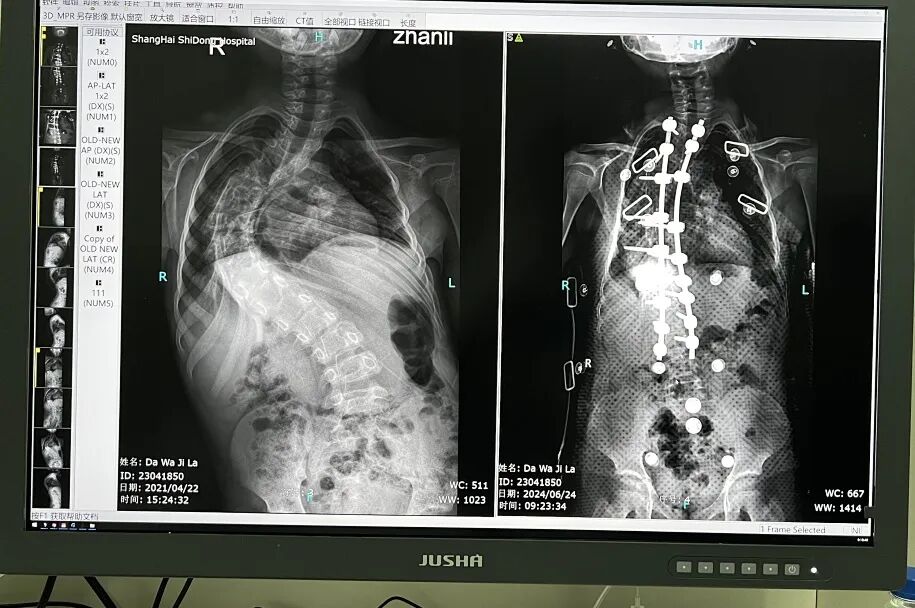

经过放射拍片检查,小达娃的脊柱侧弯矫正手术恢复情况良好。根据对比图显示,脊柱变直了,固定钢钉也都牢牢地固定在脊柱两侧。市东医院骨科主任牛云飞介绍说,“这次复诊的目的就是检查有没有内固定的松动,有没有原始侧突的加重,有没有临近节点出现新的侧突和代偿性的侧突。目前检查下来,整体上来说是非常好的,没有内固定松动,现在固定得非常牢固。”